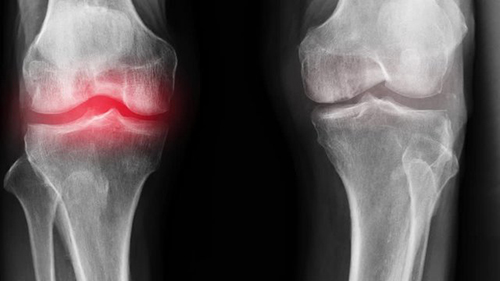

สาเหตุหลักของโรคข้อ คือการตกตะกอนของผลึกเกลือในข้อ เนื่องจากระบบไหลเวียนโลหิตและของเหลวไขข้อ (synovial fluid) เสื่อมลง:

- กรดยูริก (Urate crystals) ทำให้เกิดโรคเกาต์

- แคลเซียมเกาะกระดูก (Osteophytes) คือตัวการของโรคข้อและกระดูกกว่า 97% เช่น โรคข้ออักเสบ โรคข้อเสื่อม โรคกระดูกอ่อน โรคกระดูกพรุน โรคไขข้ออักเสบ โรคถุงน้ำในข้ออักเสบ และแม้แต่ซีสต์ของปมประสาท

เมื่อเกลือเหล่านี้เกาะอยู่บนพื้นผิวของข้อต่อ คราบเกลือเหล่านี้เหมือนกระดาษทรายที่ทำลายเนื้อเยื่อรอบโดยรอบ กระดูก และกระดูกอ่อน เมื่อผลึกโตขึ้น เกลือจะเริ่มทำลายเนื้อเยื่อของกล้ามเนื้อ เอ็น หลอดเลือด และเส้นเลือดฝอย ทำให้เกิดการอักเสบ ติดเชื้อ บวม ก่อให้เกิดการอักเสบและปวดอย่างรุนแรง

ในกรณีรุนแรง การสะสมเกลือจำนวนมากอาจทำให้กระดูกหักได้ง่ายเมื่อมีการเคลื่อนไหวอย่างกะทันหัน ส่งผลให้พิการและข้อต่อไม่สามารถเคลื่อนไหวได้